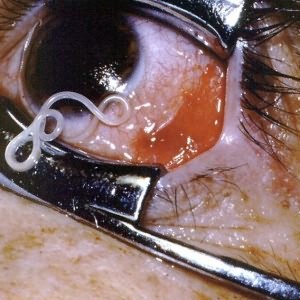

- Глазной дирофиляриоз у человека при поселении червей под веками либо в области глазного дна у человека, когда наблюдается зуд, жжение, воспаление, присутствие инородного тела в глазу, отекание, болезненность век, снижение зрения, конъюнктивит, слезотечение, присутствие чувства шевеления в области поражения, раздвоение, мушки перед глазами.

У дирофилярий есть любимые места на теле человека это органы зрения, ноги и руки, шея, лицо, грудь, мошонка. Могут появиться такие симптомы, как слабость, пассивность, тошнота, нервозность, бессонница, повышенная температура, боли в голове и в области поражения паразитом. В 50 % случаев обычно поражаются органы зрения. Человек жалуется на ощущение чего-то ползающего в глазу, у него наблюдается покраснение век и глаз, блефароспазм. При перемещении гельминта возникает боль, слезотечение и зуд. Иногда через конъюнктиву виден сам гельминт.

Справочно. При нахождении дирофилярии в глазу вокруг нее образуется гранулема, что вызывает развитие экзофтальма и диплопии. Поражение глаз приводит к ослаблению зрения. Человек способен увидеть мигрирующего паразита. Наблюдения показали, что его перемещения усиливается под воздействием тепла.

Проявления глазного дирофиляриоза связано с поражением органов зрения. Чаще всего червь селится в конъюнктиве либо подкожной клетчатке века. Несколько реже поражает белковую оболочку либо стекловидное тело.

Если капсулированный паразит располагается в подкожной клетчатке на веке, то по внешнему виду он схож с фурункулом либо халязионом. Этот дирофиляриоз у человека имеет симптомы (фото) легкого воспаления.

Стоит знать: если капсула паразита локализовалась в конъюнктиве, то проявляется слезотечение, гиперемия, конъюнктивит; когда капсула располагается в глазнице, симптомы эритема, отечность, болевой синдром, тенонит.

Исследование глаз. Офтальмолог применяет для выявления гельминтоза такие методы, как биомикроскопия и подсвечивание специальной лампой. Изучаются любые изменения в конъюнктиве и под кожей века, а также пигментация радужки и состояние хрусталика.

Что касается филяриоза глаз, то паразиты извлекаются из конъюнктивы хирургическим образом с помощью разреза органа и последующего восстановления сетчатки. Операция практикуется под обезболиванием местного характера.

При глазном дирофиляриозе основным методом лечения будет удаление гельминта с помощью операции и последующие назначение дезинфицирующих и противовоспалительных препаратов для глаз, иногда также прописываются капли дексаметазона для уменьшения воспаления. Обязательно назначаются антигистаминные средства.